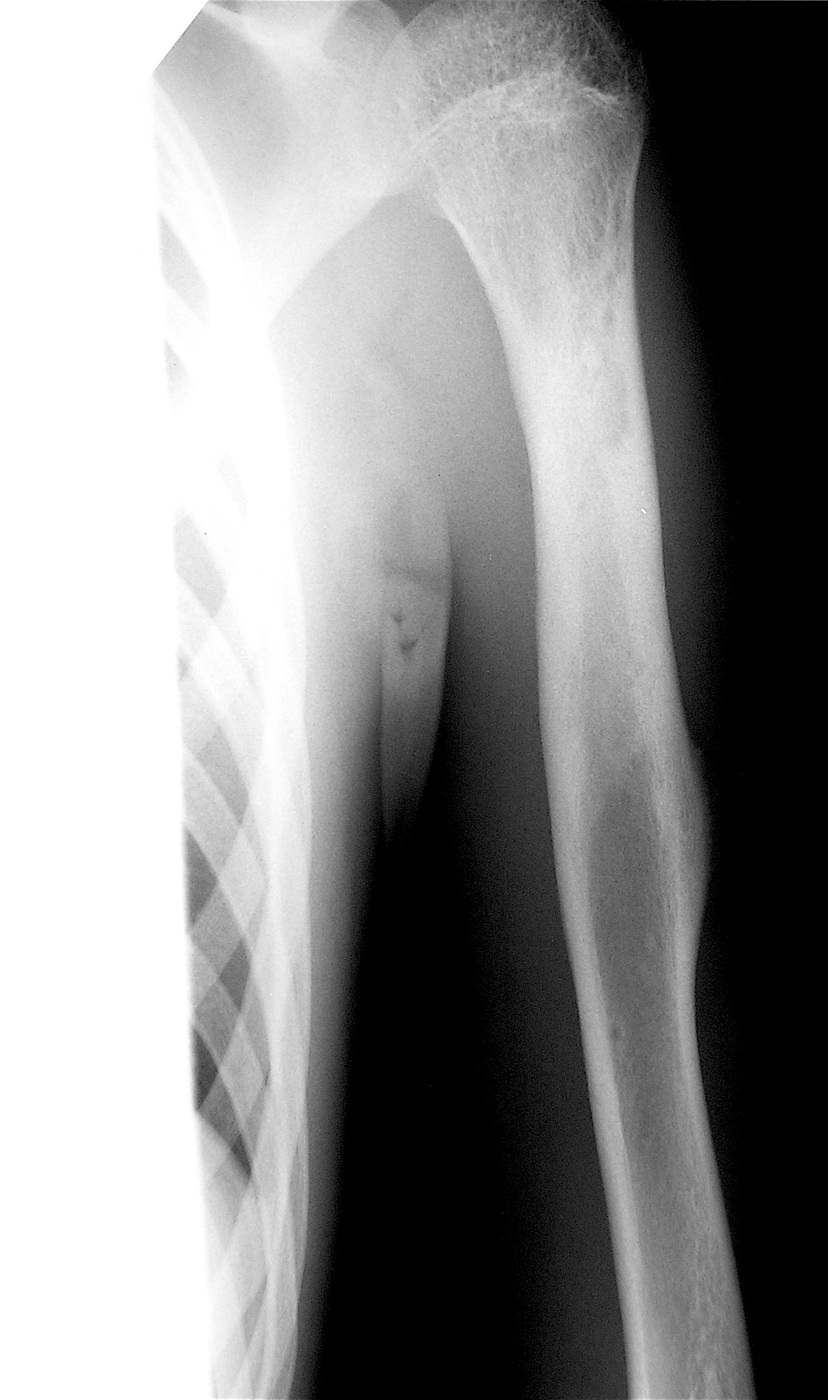

Аневризмальная киста проксимального метафиза левой плечевой кости.

Выполнена операция: экскохлеация кисты, аллопластика материалом «Лиопласт».